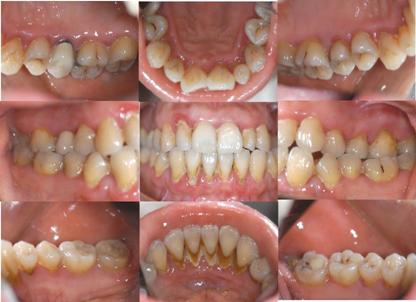

基础治疗后一年口内

本例为典型重度慢性牙周炎,具有明确的菌斑作为始动因素,全口牙周袋深度3-8mm,附着丧失4-5mm。经过1年的牙周系统治疗,疗效佳:牙龈红肿痊愈,牙周深袋除个别位点外均恢复到3mm以内。需要指出的是,对较深的牙周袋,在牙龈炎症消除后,牙龈可有一定程度的退缩,导致牙根暴露,在治疗初期会有冷热敏感不适,需要患者逐渐适应。